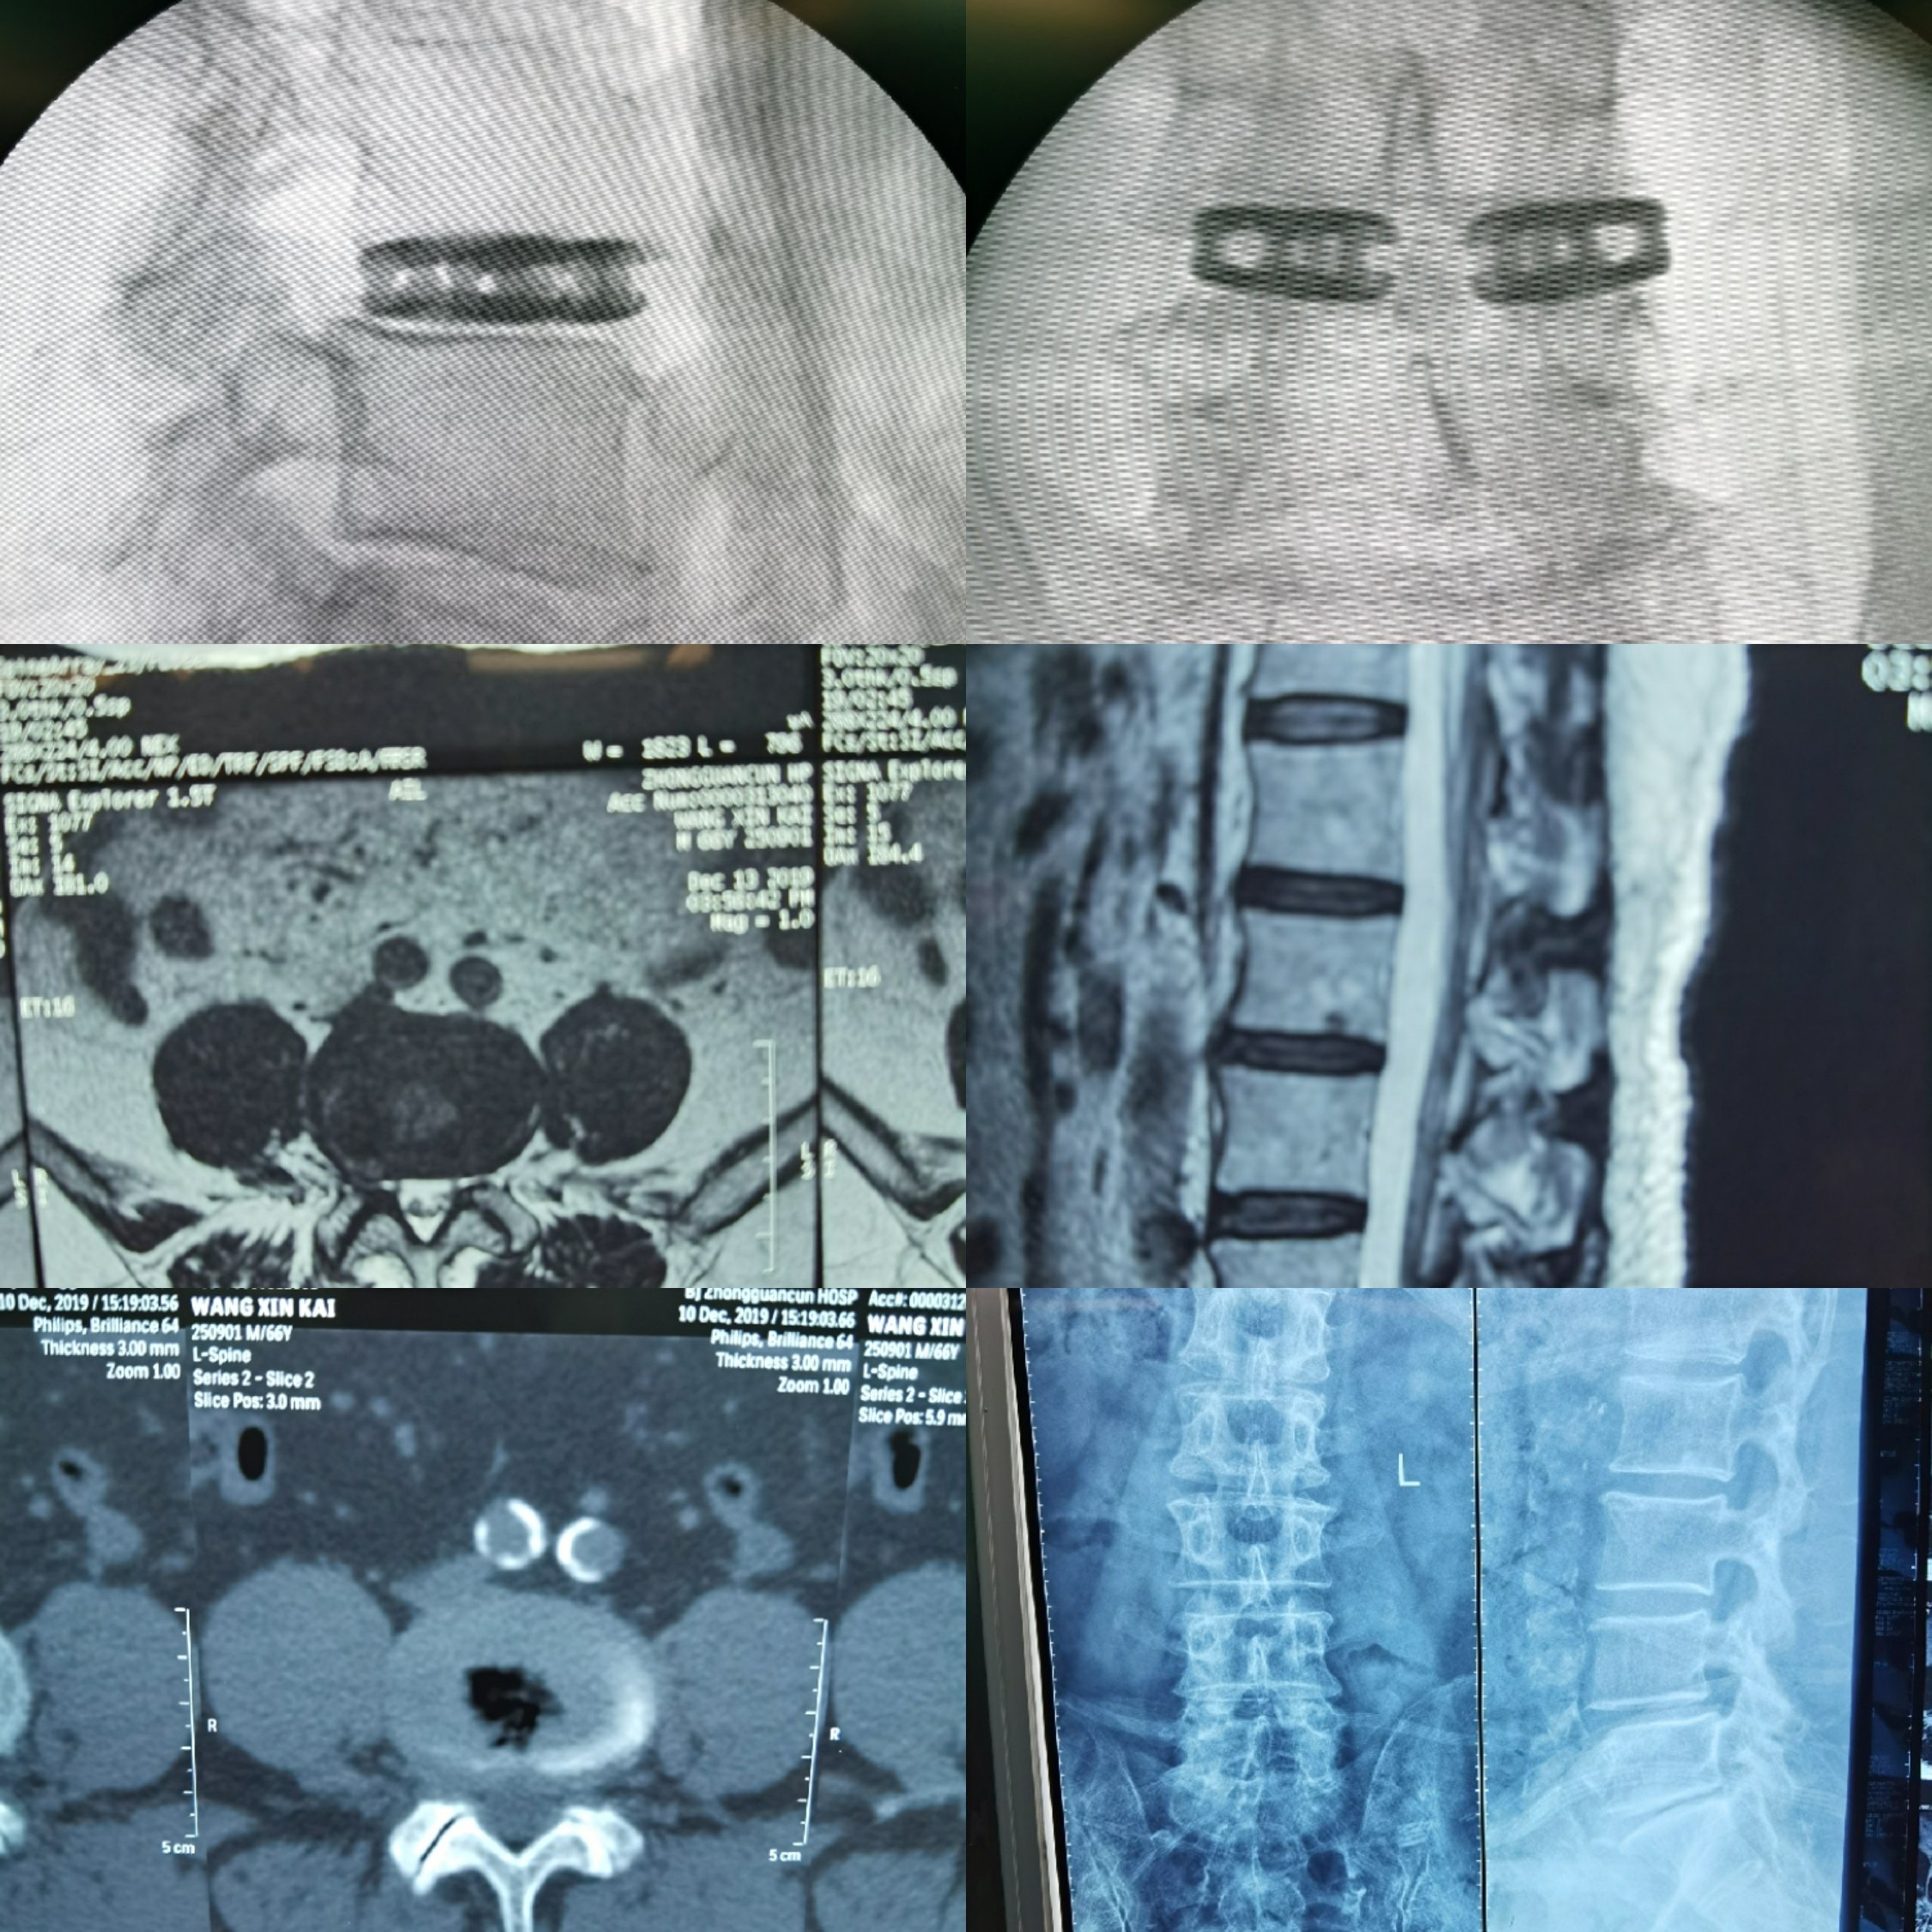

椎间孔镜技术下双枚cage腰椎间撑开融合术(wlif)病例2019.12.

图片尺寸2250x2250

科普小文章椎间孔镜技术下双枚cage腰椎间撑开融合术wlif二